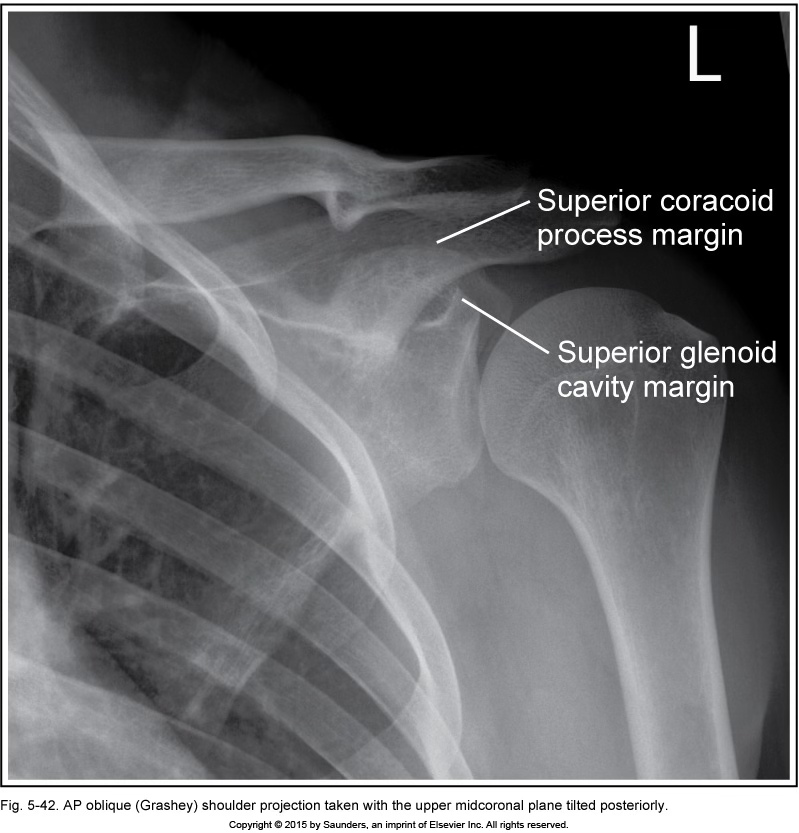

grashey

MCP tilt posteriorly

(coracoid process above glenoid cavity)